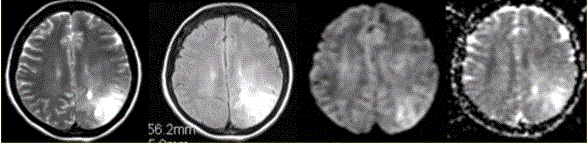

问题 女性,42岁。癫痫1个月,近期加重。无发热,无其他病史。MRI表现如下图。 有关该病MR表现,描述正确的是

选项 A.左侧顶叶不规则形长T2信号影,边界清晰 B.病变占位效应明显 C.DWI和ADC显示病变均呈高信号,提示病变的T2效应 D.病变邻近珠网膜下腔增宽 E.病变邻近脑膜增厚

答案 C